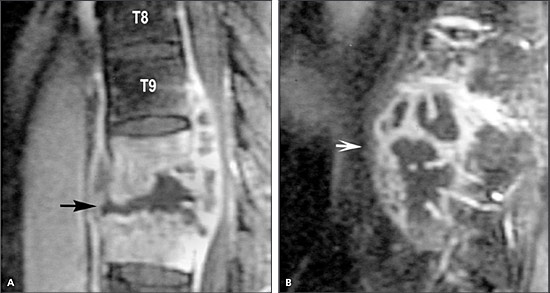

Медицинские аспекты заболеваний: рентгенологическая картина туберкулеза костей

Раздел: Снимки-откровения